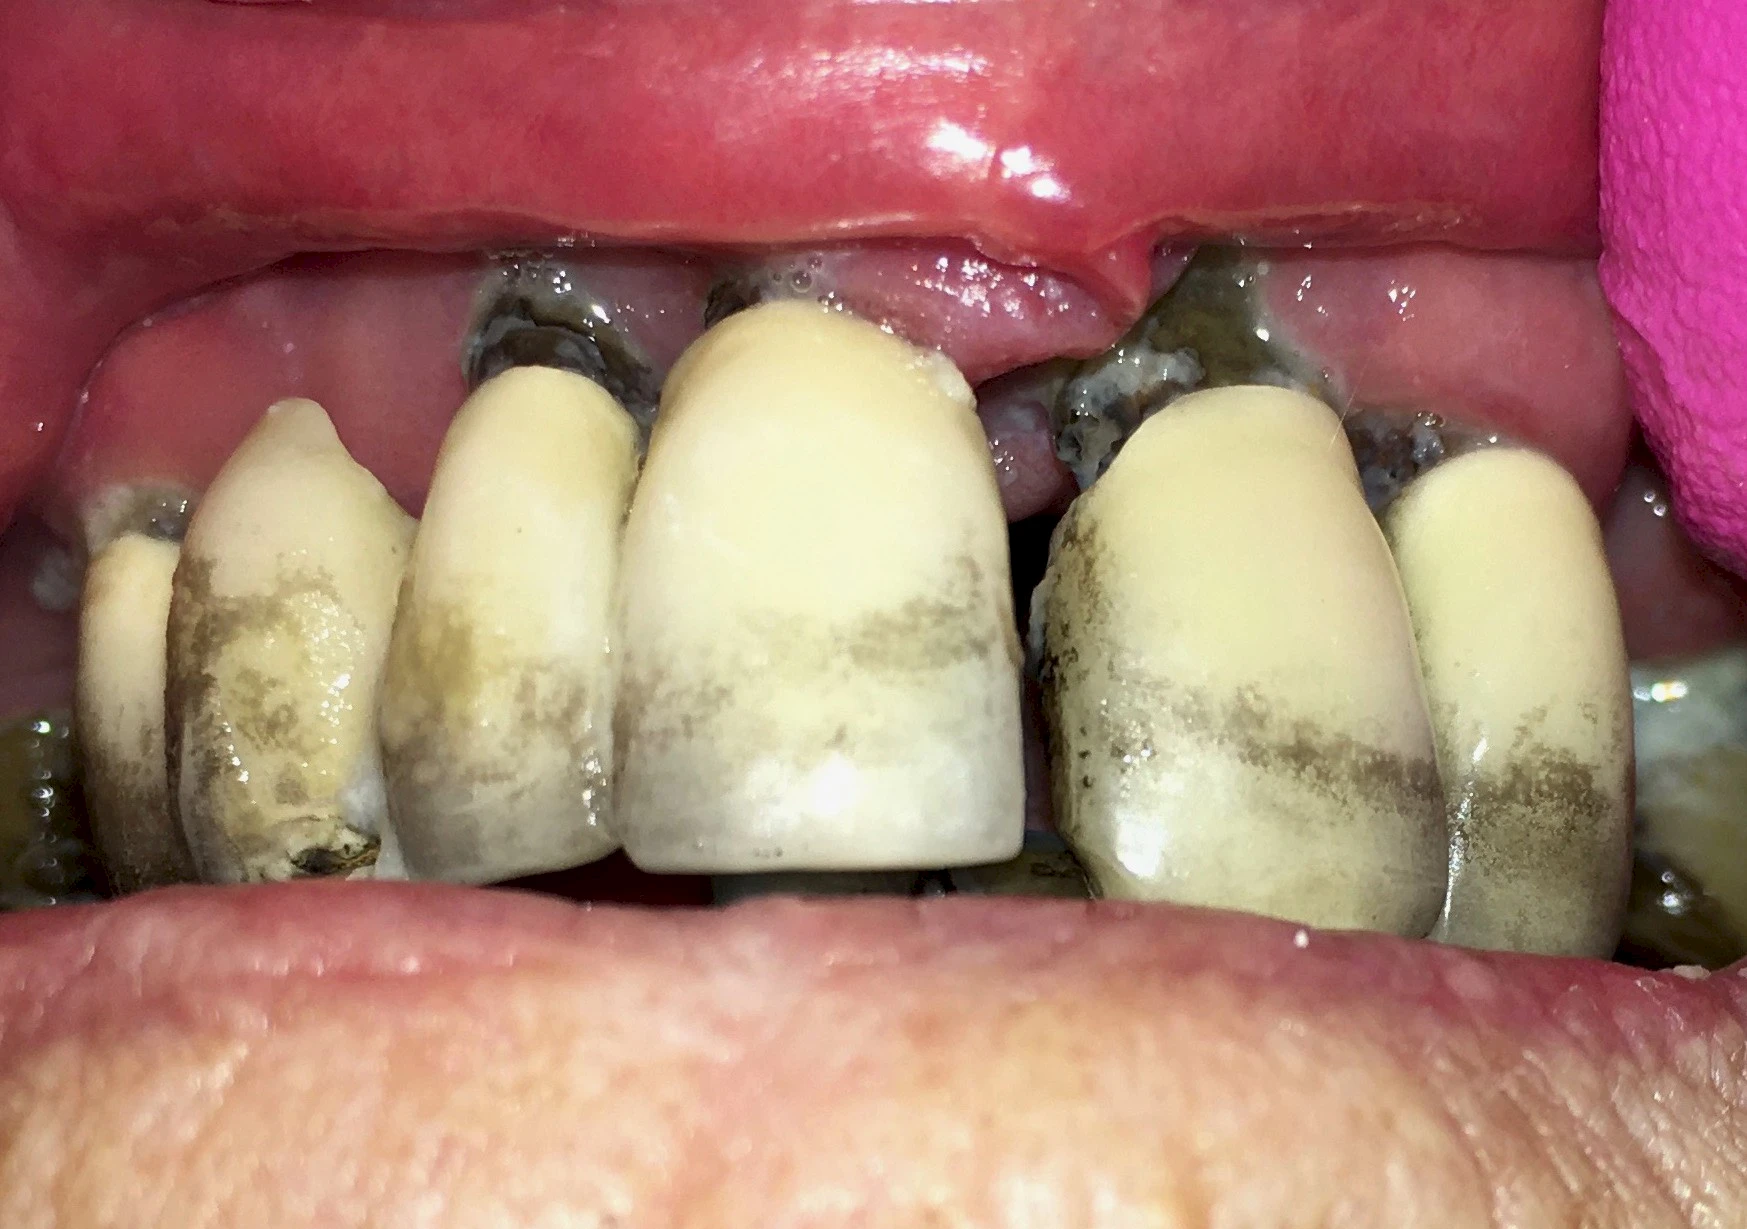

Dunkle bzw. Rötliche Verfärbung

Ist ein einzelner Zahn deutlich dunkler als die Nachbarzähne kann das ein Zeichen sein, dass der Nerv abgestorben ist. Unter Umständen wurde bereits eine Wurzelkanalbehandlung vom Zahnarzt durchgeführt. Eine Abklärung durch den Zahnarzt ist in jedem Fall sinnvoll.

Manche Medikamente wie zum Beispiel das Antibiotikum Tetrazyklin kann bei Einnahme im Zeitfenster der Zahnentwicklung auch irreversibel in die Zahnsubstanz. eingelagert werden. Tetrazyklin verfärbt die jeweils betroffenen Zähne bläulich und sollte deshalb während der Schwangerschaft und bei Kindern nicht verordnet werden.